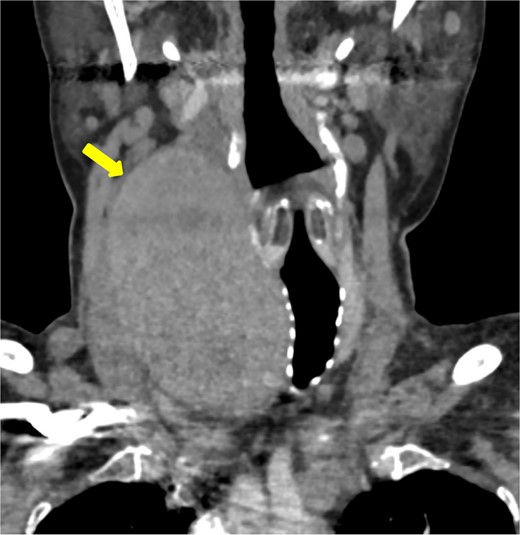

This case study describes a 76-year-old female with a history of type 2 diabetes and hypertension for fifteen years, controlled by her medication. She was swimming when she noted a sudden swelling in her neck. She presented to the emergency department of our hospital with right neck swelling for one-day duration. Physical examination shows a vitally stable patient with a localized neck mass not movable with swallowing and not associated with compressive symptoms. Computed tomography (CT) scan showed significant enlargement of the right thyroid lobe with heterogeneous predominantly hyperdense mass with mass effect on the airway with leftward deviation of the trachea (Fig. 1). Pre-operative CT Angiography showed active extravasation (Fig. 2). Also, there is a suspected right thyroid artery arching over the hematoma. The appearance of the artery raised the possibility of this artery being the cause of the hematoma. Then, a diagnostic angiogram was performed, which showed a dilated, ectatic-looking superior thyroid artery with flow into the hematoma, confirming the source of the hematoma. The patient successfully underwent angioembolization and hematoma evacuation without complications. During the procedure, an unexpectedly large solid component resembling thyroid tissue and a sac surrounding the hematoma were found. The patient was admitted to the Surgical Intensive Care Unit for post-operative monitoring and to prevent potential airway obstruction. The resected specimen was sent for further evaluation by pathology. Gross examination shows large dark brown hemorrhagic mass with thyroid tissue identified measuring 7.5 cm × 0.5 cm. Histopathology examination of the specimen revealed thyroid tissue with extensive hemorrhage and irregular dilated vascular spaces, as well as capillary-like vessels present in thyroid parenchymal tissue. Few thick-walled blood vessels were seen. These vascular channels are lined by bland endothelial cells (Fig. 3A, B). No cellular atypia, mitosis or solid growth pattern was observed. The vascular lining is diffusely positive for CD34, CD31, D2–40, and FLI1 (Fig. 3C, D). Given the above features of histopathology and immunohistochemistry studies, the diagnosis was compatible with primary thyroid hemangioma. Five months post-surgical resection, the patient’s follow-up indicates that she is in good health with no neck swelling, hoarseness of voice, or difficulty tolerating a regular diet. Her wound has healed without any signs of infection.

CT angiography shows active extravasations along the posterior aspect of the right thyroid lobe mass.